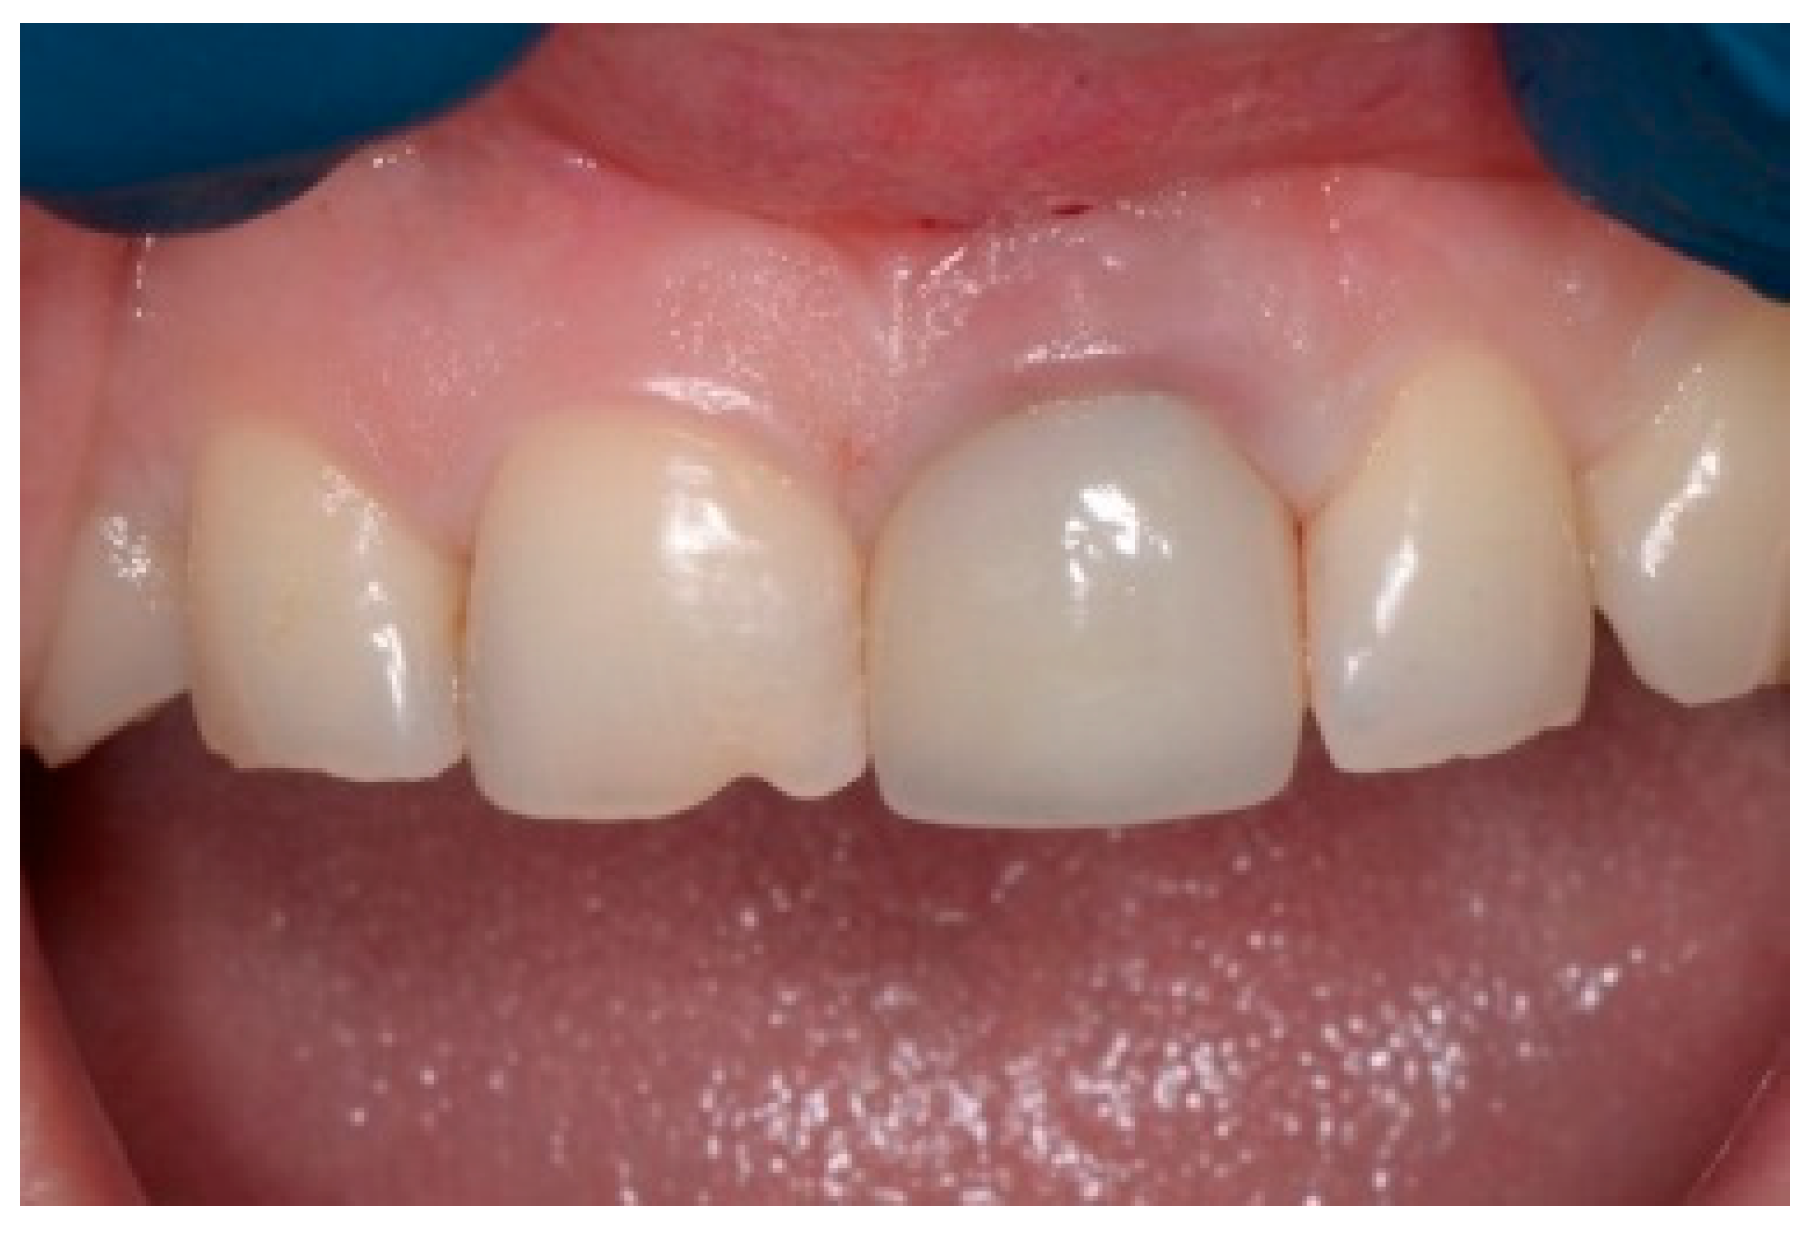

A 43-year-old female patient in good health and a non-smoker presented with a history of endodontic failure of the maxillary central incisors. She was interested in the replacement of her teeth with endosseous implants. The teeth had previously been treated endodontically with no lesion regression. Endodontic surgery had also failed. Clinical examination revealed class 1 mobility and a scar on the soft tissue above the maxillary anterior teeth. Radiographic examinations revealed the presence of chronic periapical lesions associated with teeth number 8 and 9, and clinically there was minimal remaining tooth structure (Figure 1). A treatment plan involving the placement of two immediate implants followed by future ceramic crowns was presented and accepted by the patient.

Figure 1.

Clinical view of existing maxillary incisors.